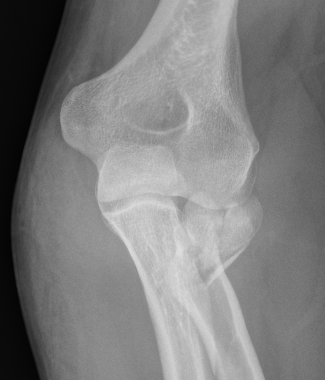

Indications for surgery

> 30o angulated

Displacement